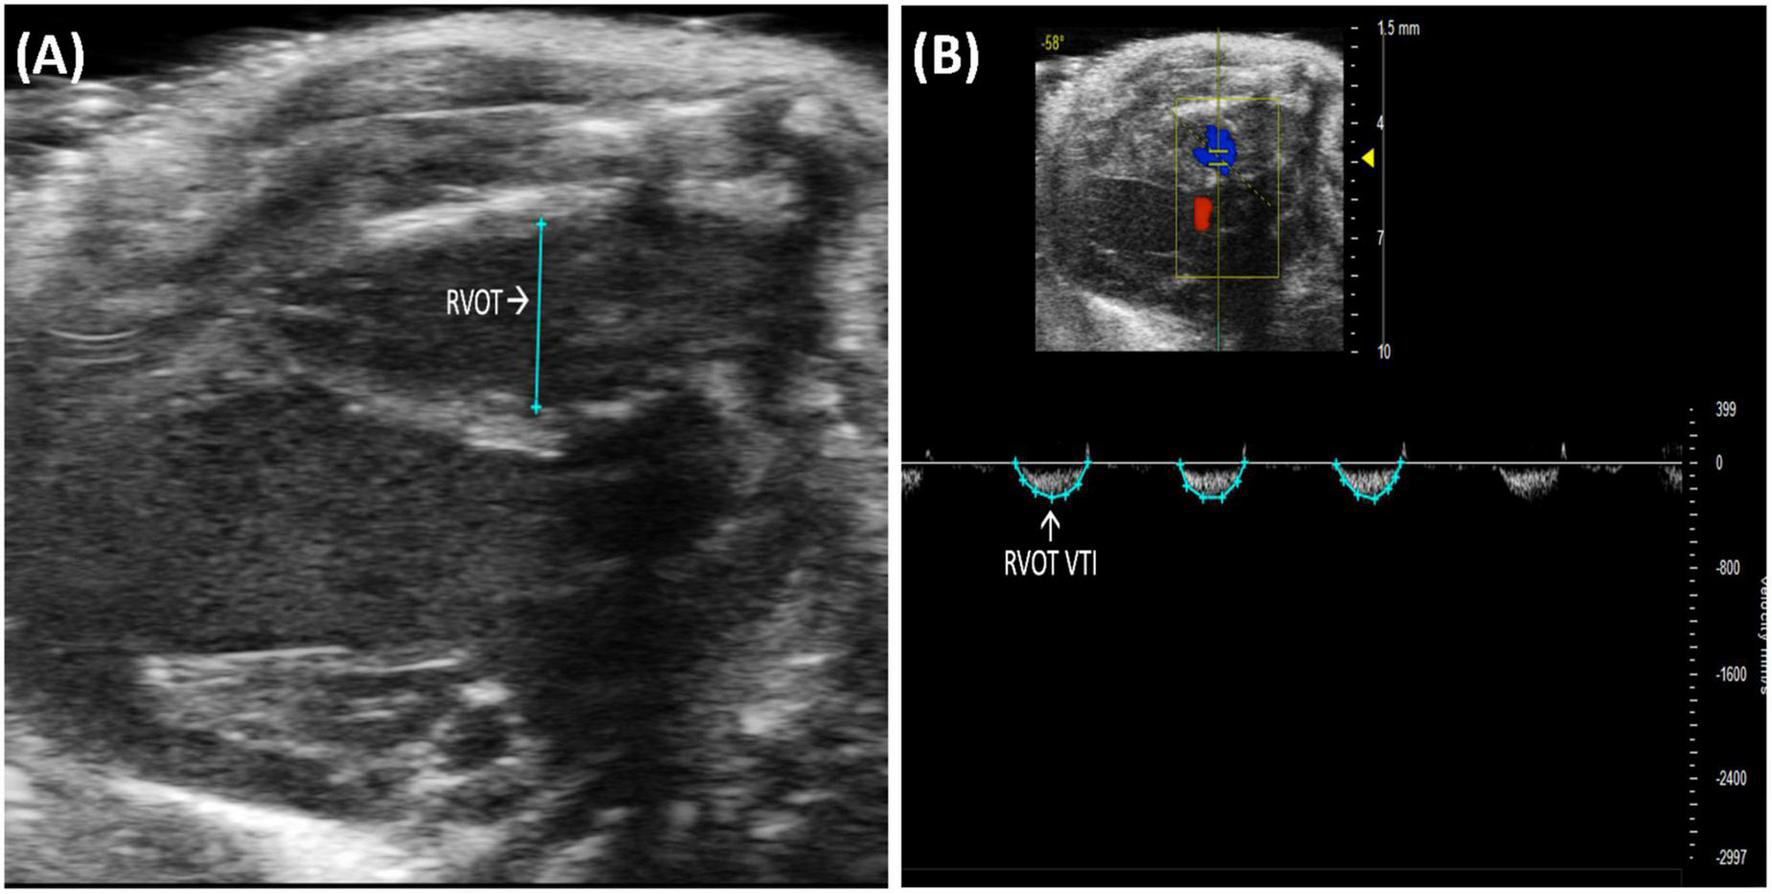

2.2.1.2 Right ventricular outflow tract length

Right ventricular outflow tract (RVOT) length is the measurement of the right ventricular outflow tract at end diastole. It can be measured by selecting “RVOT” in a PLAX B-mode image containing the RV (Figure 3A). The RVOT is located just proximal to the PV. RVOT is another indicator of RV size (2); a dilated RVOT suggests right ventricular volume overload.

FIGURE 3

(A) Right ventricular outflow tract (RVOT) measures the size of the right ventricular outflow tract at the end of diastole and is acquired and analyzed in B-mode of the parasternal long axis (PLAX) view. (B) Right ventricular outflow tract velocity time integral (RVOT VTI) measures blood flow through the right ventricular outflow tract (RVOT) and is acquired by pulsed wave (PW) Doppler imaging of the RVOT in B-mode of the parasternal long axis (PLAX) view.

2.2.1.3 Right ventricular outflow tract velocity time integral

Right ventricular outflow tract velocity time integral (RVOT VTI) is a measurement of blood flow through the RVOT. It can be measured as the area under the curve in a pulsed wave (PW) Doppler image of PLAX with the yellow marker on the flow of the RVOT (Figure 3B). Mean velocity, mean gradient, peak velocity, and peak gradient are automatically calculated. RVOT VTI is a surrogate for RV stroke volume (SV), hence, the ratio of RVOT VTI to pulmonary artery systolic pressure represents pulmonary arterial compliance, an important measure for pulmonary arterial hypertension (PAH) (4). Right ventricular systolic pressure is equal to pulmonary artery systolic pressure (5) and can be measured by right heart catheterization in mice. RVOT and RVOT VTI can be used to calculate right ventricular SV and cardiac output (CO).